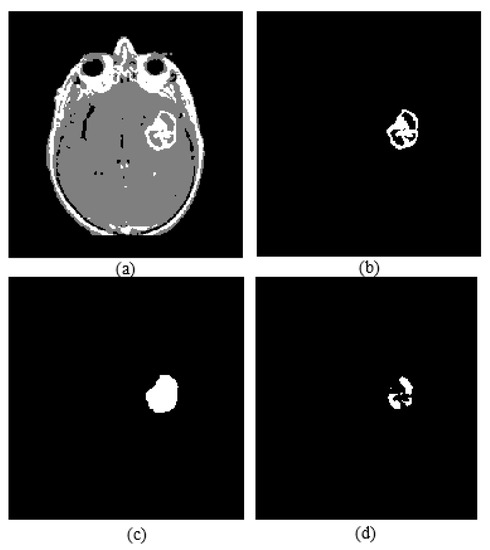

Active core segmentation and the volume estimation stage involve masking and FCM clustering operations, as outlined in Figure 11. The T1C image is converted to a binary image via FCM and a morphological opening operation (Figure 12c), and then skull stripping and whole tumor masks (Figure 12d,e) are applied on this image to obtain the enhancing/active core (Figure 12f). To obtain the necrotic/cystic core, a morphological closing operation is applied on the active core region (Figure 13c), then the active core is subtracted from this image (Figure 13d).

Figure 12.

(a) T1C image; (b) fuzzy c-means clustering result; (c) binary image including active core; (d) skull stripping mask; (e) whole tumor mask; (f) enhancing tumor.

Figure 13.

(a) FCM clustering result of a T1C image; (b) enhancing tumor; (c) image closing result; (d) necrotic core.